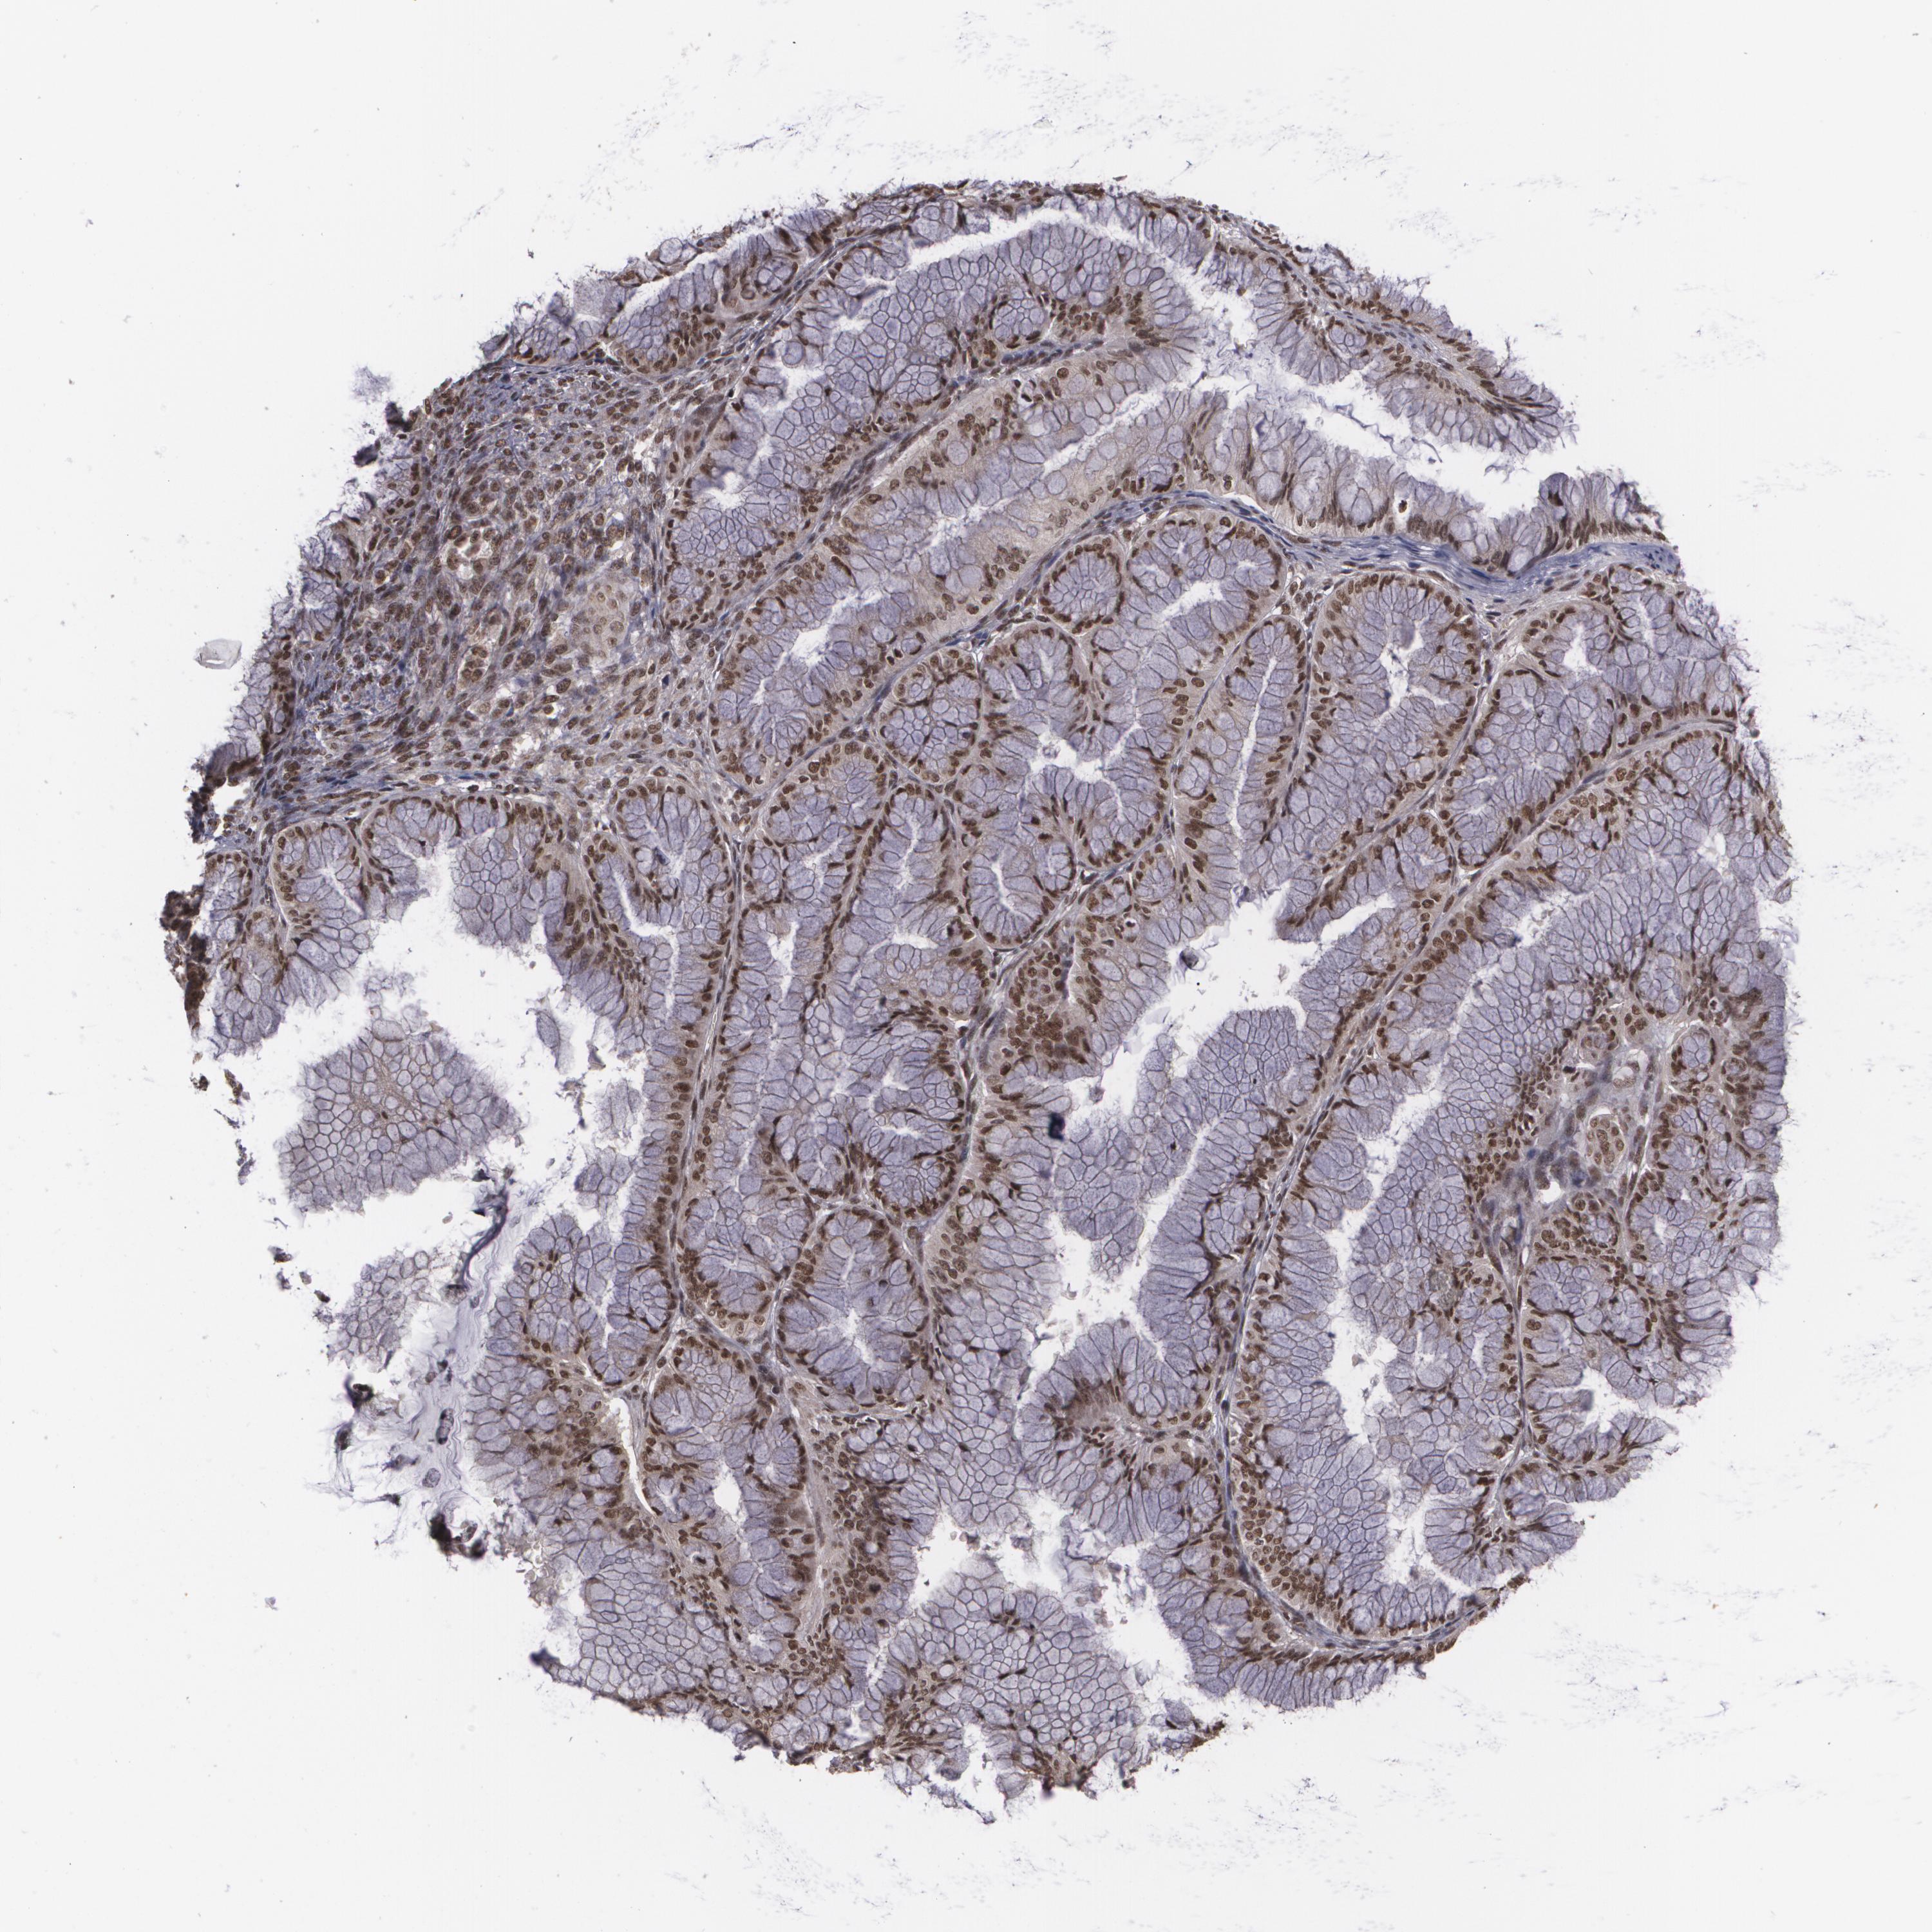

OVARIAN CANCER - Protein expressioni

A mouse-over function shows sample information and annotation data. Click on an image to view it in a full screen mode. Samples can be filtered based on level of antibody staining by selecting one or several of the following categories: high, medium, low and not detected. The assay and annotation is described here.

Note that samples used for immunohistochemistry by the Human Protein Atlas do not correspond to samples in the TCGA dataset.

Antibody stainingi

Antibody staining in the annotated cell types in the current human tissue is reported as not detected, low, medium, or high, based on conventional immunohistochemistry profiling in selected tissues. This score is based on the combination of the staining intensity and fraction of stained cells.

Each image is clickable and will lead to virtual microscopy that enables deeper exploration of all samples and also displays staining intensity scores, fraction scores and subcellular localization as well as patient and tissue information for each sample.

Antibody CAB002003

Staining

High

Medium

Low

Not detected

Intensity

Strong

Moderate

Weak

Negative

Quantity

>75%

75%-25%

<25%

None

Location

Nuclear

Cytoplasmic/membranous

Cytoplasmic/membranous,nuclear

Cystadenocarcinoma, mucinous, NOS

Carcinoma, endometroid

Cystadenocarcinoma, serous, NOS